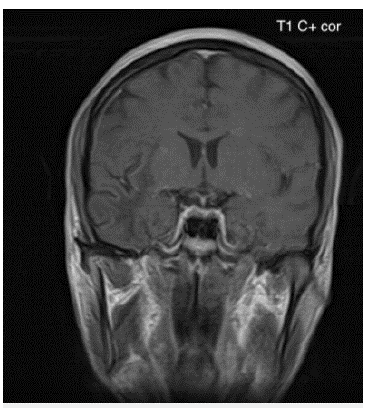

Ante el cuadro clínico y los hallazgos descritos en el examen físico se realizó una imagen de resonancia magnética (IRM) cerebral contrastada (figuras 1-3) en la cual se documentó la presencia de hiperintensidades extensas a nivel subcortical que comprometían la sustancia blanca hemisférica cerebral derecha con una distribución en los lóbulos frontal, parietal y temporal. Adicionalmente, se observó compromiso de la sustancia blanca en la región frontotemporal izquierda que comprometía las fibras en U. No se identificaron áreas de sangrado ni tampoco la presencia de masas ni realces anormales con el medio de contraste.

Figura 1B Imagen de resonancia magnética cerebral contrastada corte coronal en secuencia T1 al mismo nivel de la figura 1A: Lesiones hipointensas de extenso compromiso de la sustancia blanca subcortical difusa bilateral de predominio derecho en lóbulo temporal.

Por medio de la IRM cerebral contrastada, especialmente en la secuenciación potenciada en T2 y recuperación de la inversión atenuada de fluido (FLAIR por sus siglas en inglés), fue posible identificar las lesiones típicas de la enfermedad. Se trata de lesiones múltiples bilaterales, hiperintensas, asimétricas, de morfología irregular, que comprometen la sustancia blanca subcortical y yuxtacortical del cerebro, incluyendo las fibras en U, delineando los bordes de la corteza sin producir efecto de masa ni realce con el medio de contraste 3,8,9. En la secuenciación potenciada en T1 estas lesiones se presentan hipointensas.